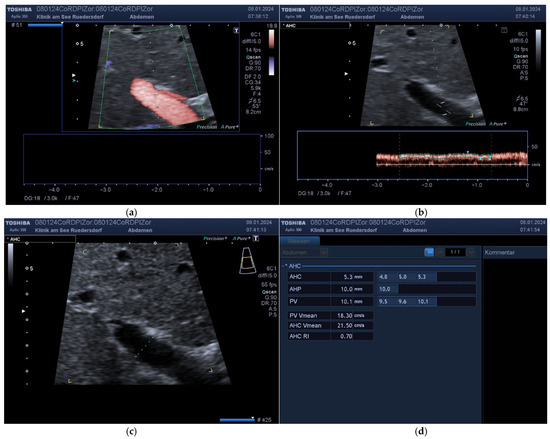

2.3.1. Determination of Vessel Diameter

2.3.2. Location of the Probe, Insonation Angle, and Doppler Window